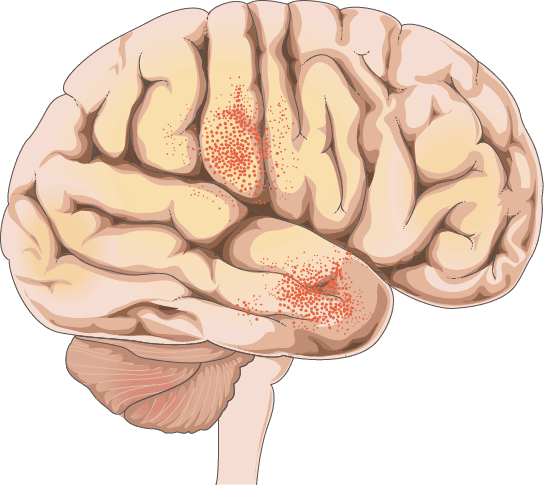

HSV-1-Enzephalitis:

Akuter Verlauf (Std. - wenige Tage) mit fulminanter Klinik und hoher Letalität ohne Therapie

Häufig epileptische Anfälle und psychiatrische Symptome

Meist unilaterale Läsionen im mesialen Temporallappen und limbischen System, z.T. hämorrhagisch